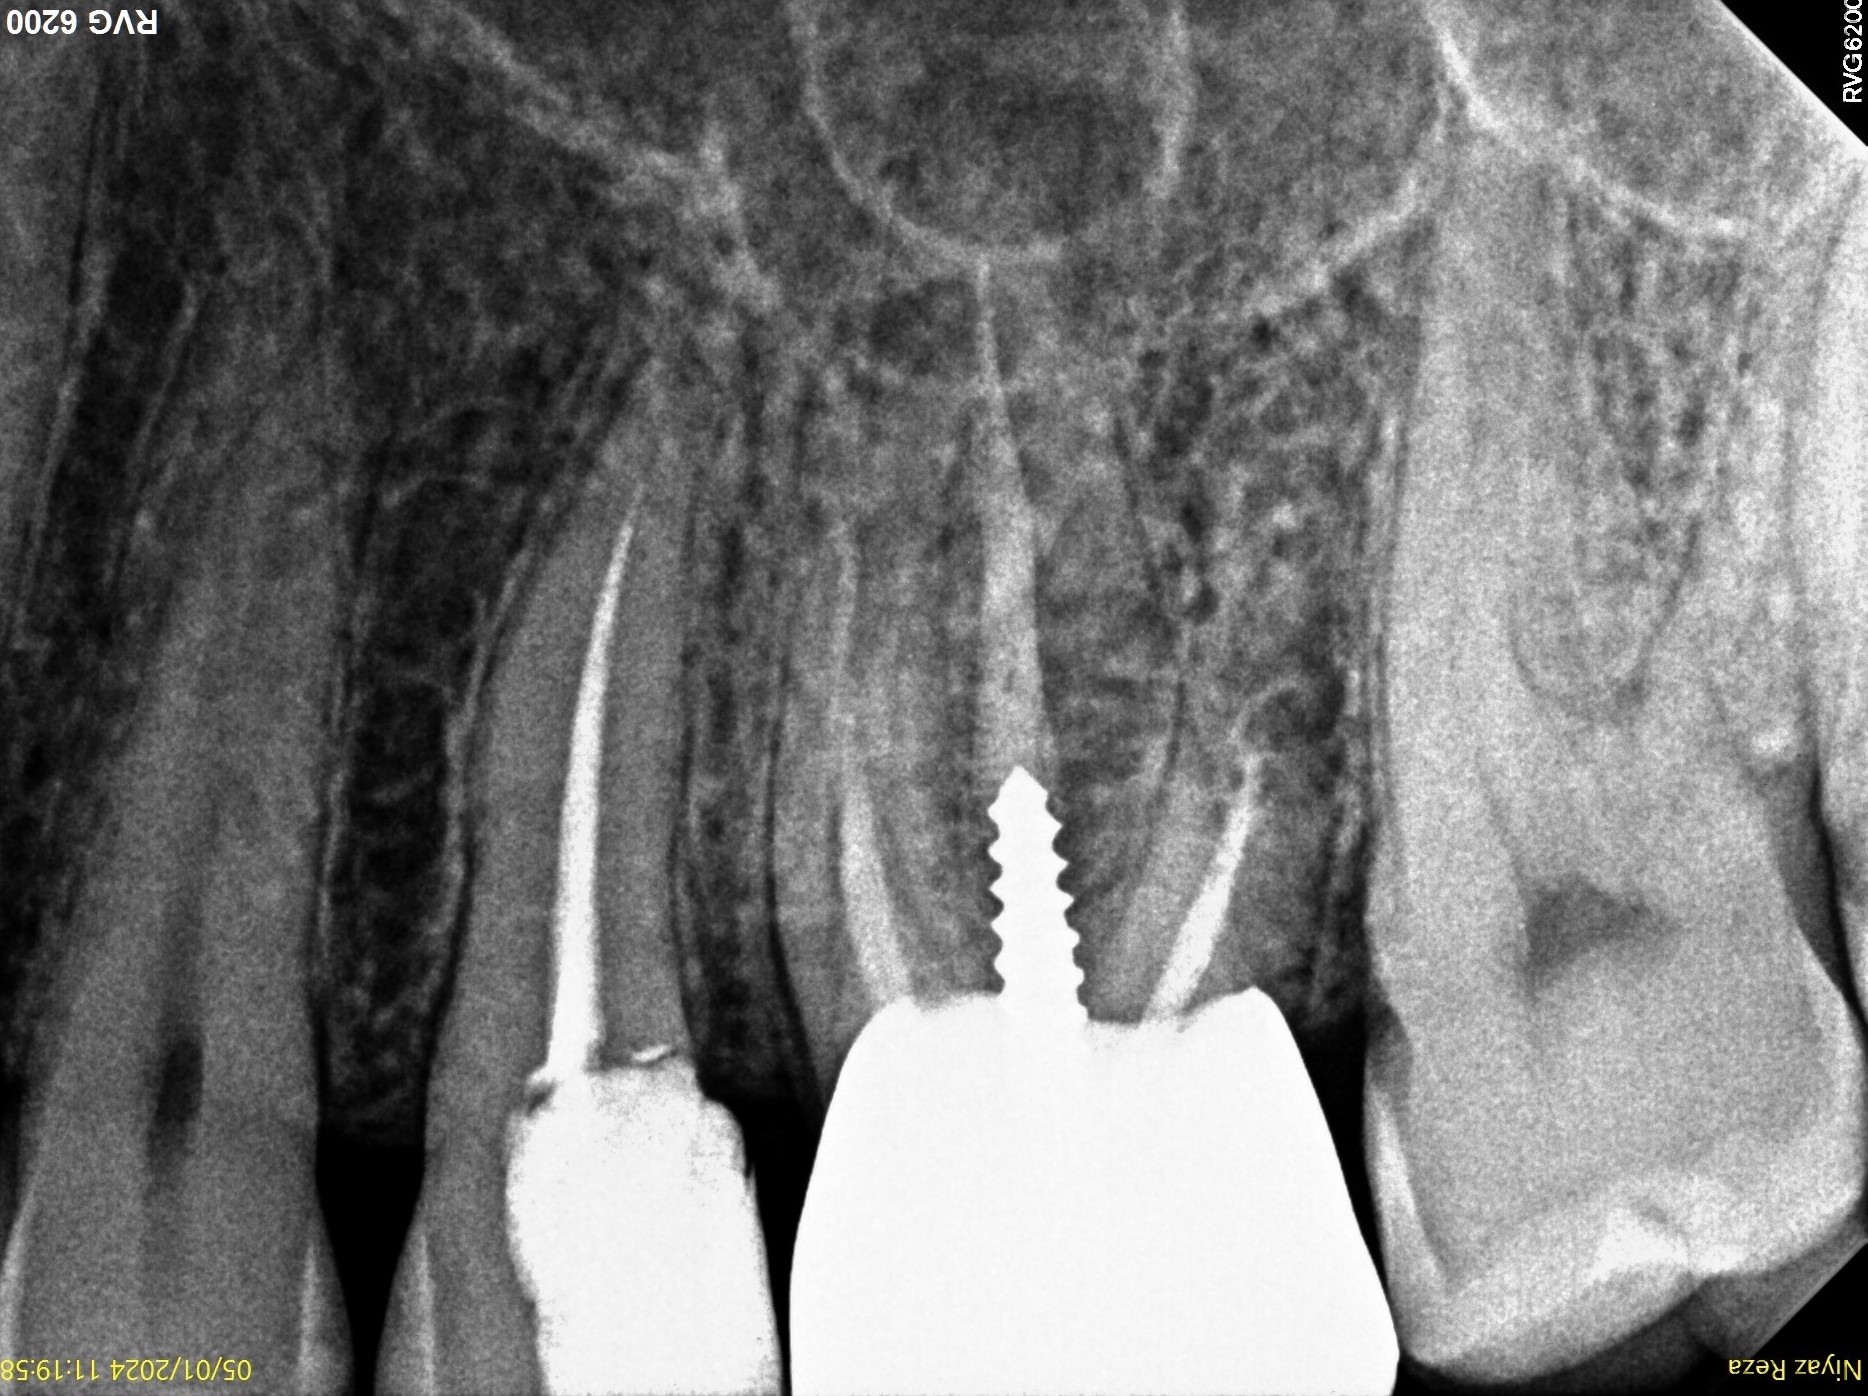

7. What condition can be selected or the root canal treatment of tooth # 4.6?

8. What condition can be selected or the root canal treatment of tooth # 3.6?